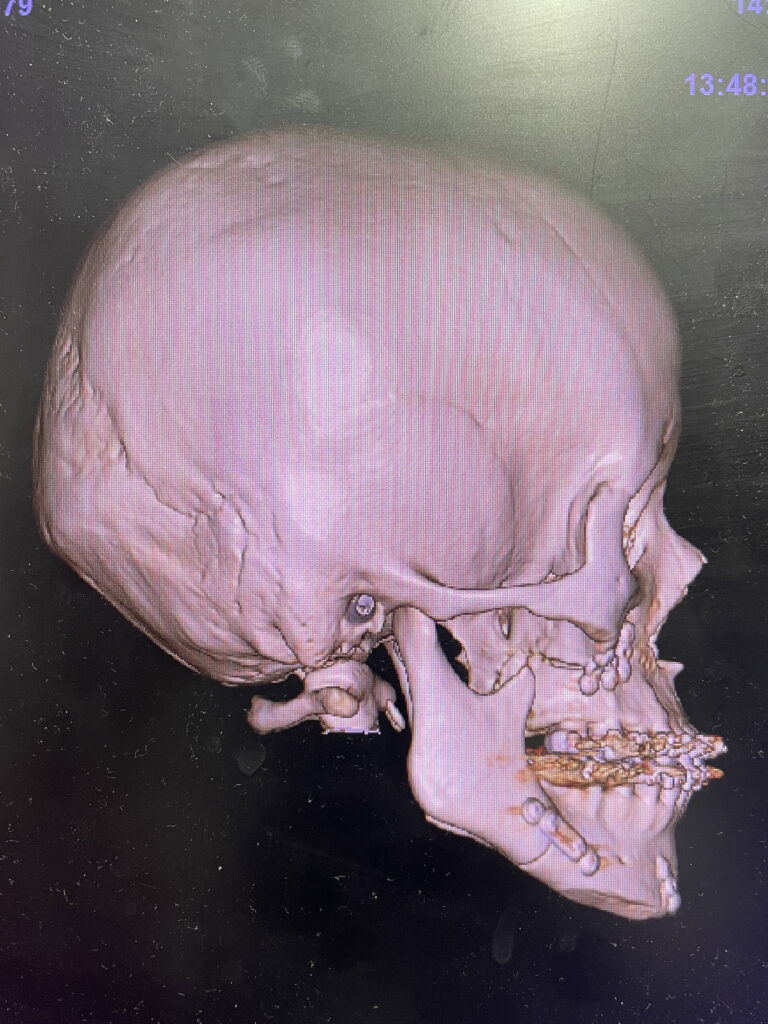

レントゲンを用いて骨格の特徴を把握します。白線の輪郭は標準的な骨格を表しています。標準骨格と比べると、下顎が前に出ていて、なおかつ垂直方向に長いことがわかりました。

下顎はSSROで後方に移動させ、上顎は鼻下の陥没感を改善するために上顎前歯の先端を回転中心として時計回転させて鼻下の骨を前方に出す計画としました。顎先は中抜きオトガイ形成で垂直方向の長さを短縮することにしました。

白線の標準骨格に一致するように骨の移動量を決めていきます。上顎は鼻下で2mm前進し、臼歯部で2mmほど上方に移動させます。全体として上下顎は時計回転することになります。顎先は4mmの中抜き短縮です。